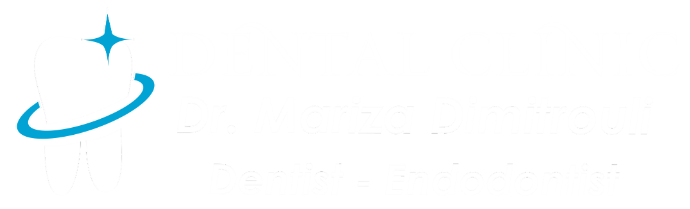

Dental fillings of primary teeth

BEFORE

BEFORE